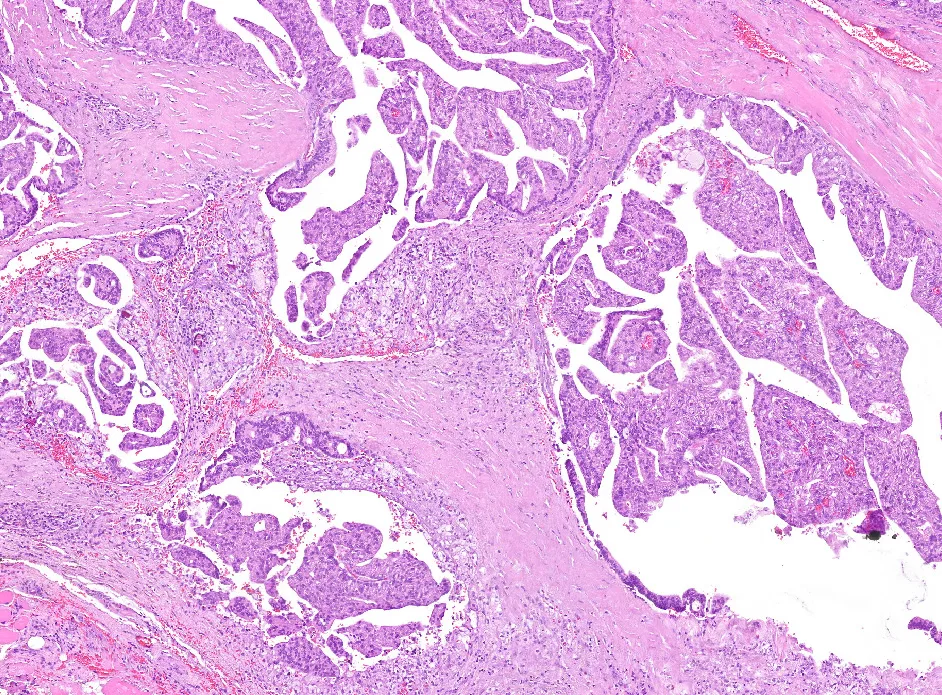

4-H&E4

Diagnóstico: Adenocarcinoma mucinoso, anteriormente denominado cistoadenocarcinoma papilar, de grado intermedio de localización amigdalar.

- Se trata del equivalente maligno del cistoadenoma, carece de los rasgos histopatológicos específicos de otros carcinomas salivales con crecimiento quístico. (PMID: 30918612 y PMID: 27510680)

- Histológicamente se caracterizan por áreas quísticas y sólidas con múltiples proyecciones papilares luminales que tienen un núcleo fibrovascular y están revestidas por células epiteliales cúbicas, columnares o secretoras de moco. Inmunohistoquímicamente es CK7, CEA y EMA positivo, siendo negativo para otros marcadores de glándula salival. (PMID: 35252049)

- Algunos autores hablan de un sistema de clasificación dual, en neoplasias de bajo o alto grado, estas últimas suelen tener características localmente agresivas con invasión estromal, atipia citológica, tasa mitótica alta, necrosis y ausencia de características papilares. Aunque nosotros hemos gradado la neoplasia acorde a los parámetros de gradación de la OMS (grado intermedio). (PMID: 30918612)